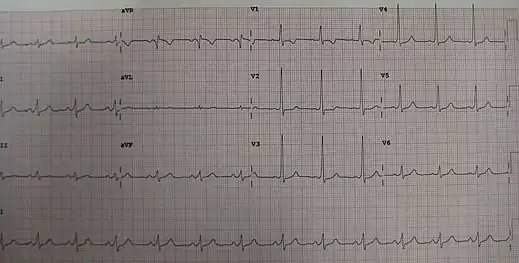

| A characteristic "delta wave" (arrow) seen in a person with Wolff–Parkinson–White syndrome. Note the short PR interval. | |

| Diagnostic method | Electrocardiogram shows a short PR interval and a wide QRS complex from a delta wave[3] |

The cause of WPW is typically unknown and is likely due to a combination of chance and genetic factors.[2] A small number of cases are due to a mutation of the PRKAG2 gene which may be inherited in an autosomal dominant fashion.[2] The underlying mechanism involves an accessory electrical conduction pathway between the atria and the ventricles.[1] It is associated with other conditions such as Ebstein anomaly and hypokalemic periodic paralysis.[1] The diagnosis of WPW occurs with a combination of palpitations and when an electrocardiogram (ECG) show a short PR interval and a delta wave.[3] It is a type of pre-excitation syndrome.[3]

WPW is commonly diagnosed on the basis of the electrocardiogram in an asymptomatic individual. In this case, it is manifested as a delta wave, which is a slurred upstroke in the QRS complex that is associated with a short PR interval. The short PR interval and slurring of the QRS complex are reflective of the impulse making it to the ventricles early (via the accessory pathway) without the usual delay experienced in the AV node.

When an individual is in normal sinus rhythm, the ECG characteristics of WPW are a short PR interval (less than 120 milliseconds in duration), widened QRS complex (greater than 120 milliseconds in duration) with slurred upstroke of the QRS complex, and secondary repolarization changes (reflected in ST segment-T wave changes).

In individuals with WPW, electrical activity that is initiated in the SA node travels through the accessory pathway, as well as through the AV node to activate the ventricles via both pathways. Since the accessory pathway does not have the impulse slowing properties of the AV node, the electrical impulse first activates the ventricles via the accessory pathway, and immediately afterwards via the AV node. This gives the short PR interval and slurred upstroke of the QRS complex known as the delta wave.

In case of type A pre-excitation (left atrioventricular connections), a positive R wave is seen in V1 ("positive delta") on the precordial leads of the electrocardiogram, while in type B pre-excitation (right atrioventricular connections), a predominantly negative delta wave is seen in lead V1 ("negative delta").[13]